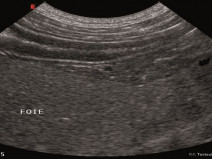

• Les maladies hépatiques du chat : diagnostic et prise en charge

Etre capable de

• choisir et interpréter les analyses sanguines dans le diagnostic des affections hépatiques du chat

• diagnostiquer et prendre en charge une lipidose hépatique chez le chat diagnostiquer et prendre en charge une cholangiohépatite féline

• donner des conseils diététiques appropriés en cas d’atteinte hépatique chez le chat

• choisir et interpréter les prélèvements (cytoponctions, biopsies) dans le diagnostic des affections hépatiques du chat.

• Echographie du tube digestif et de ses annexes (foie - pancréas) - MODULE SATELLITE A : Lyon

• réaliser un examen échographique de l’abdomen

• utiliser les principes de l’échographie (ultrasons, formation de l’image) pour optimiser l’acquisition de l’image (réglages machine) et identifier des artefacts classiques en échographie

• standardiser l’examen : préparation, orientation, procédures d’acquisition des coupes

• identifier les différents organes abdominaux et réaliser sur chacun les coupes standard

• reconnaître les différentes structures anatomiques normales.

En savoir plus

2f540e8ebc8bb22e35b5e28a128c8b15

Du 15 au 16 octobre 2016

DARDILLY (69570)

Imagerie Médicale

G.E.I.M.

124